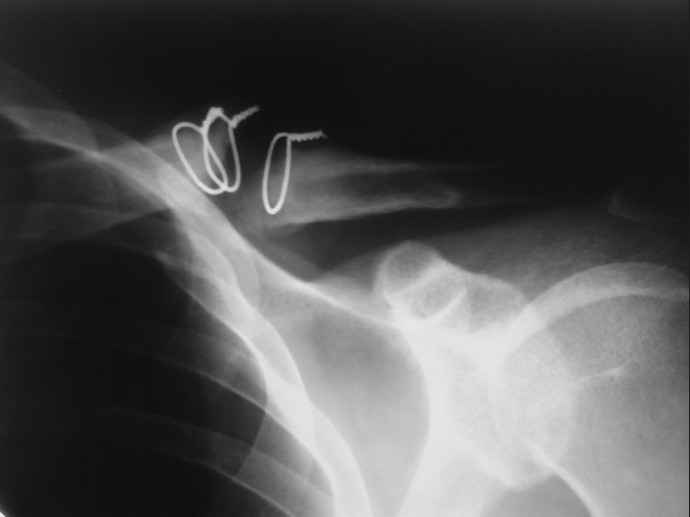

Ложный сустав ключицы

34 года, около года назад,оперирован в одном из городских ЛПУ области.Через 2 мес. удалён (стержень Богданова?Спица ?).Активно занимался спортом,в последнее время около месяца (со слов стало беспокоить патолог.подвижность и хруст). На снимках ложный сустав...

R-гр в приложении